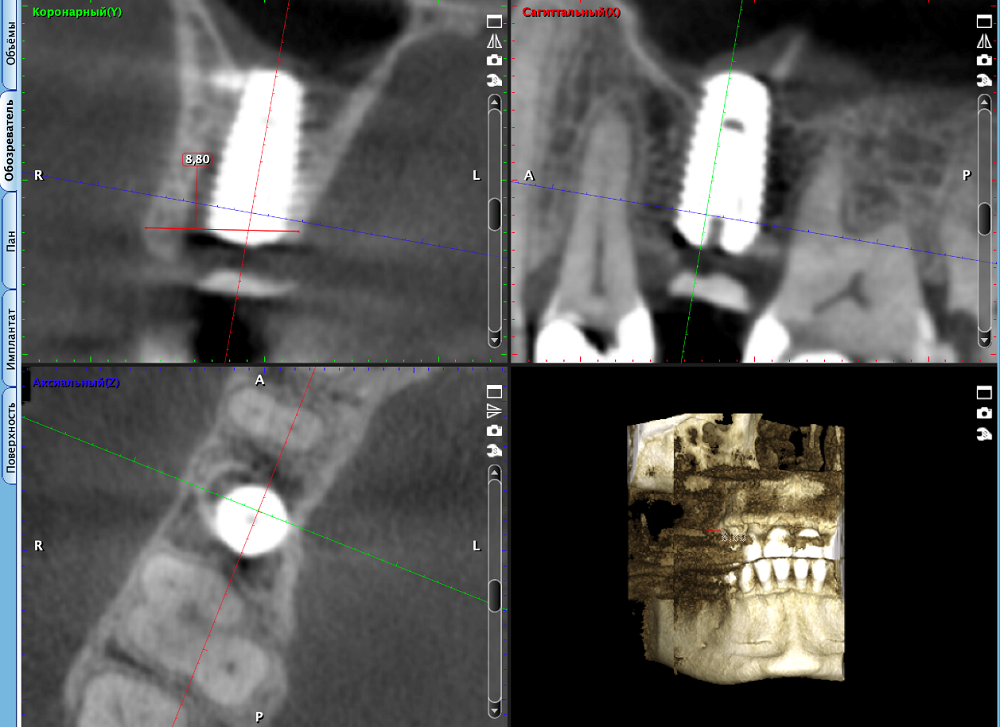

Дентальная имплантация в классическом исполнении с момента удаления зуба до установки имплантата занимает в среднем от трех до шести месяцев. В современной стоматологии существуют методы, позволяющие сократить сроки планируемого лечения. Поэтому в ряде случаев по показаниям используют методику установки имплантата сразу после удаления зуба – одномоментную имплантацию.

Такой способ проведения операции позволяет сохранить объем костной и мягкой ткани после удаления зуба и исключает применение костной пластики в дальнейшем. Практика доказывает: одномоментная имплантация является одним из факторов успеха для сохранения индивидуальных анатомических особенностей контура десневой и костной ткани после удаления зуба, – поясняет профессор НИУ «БелГУ» Ирина Рыжова.

В НИУ «БелГУ» разработали и запатентовали новый эффективный способ реплантации фрагмента удаленного зуба в области одномоментной имплантации, являющийся наиболее щадящим для пациента.

Разработанный способ позволяет сохранить объем и контур мягких тканей в области установленного имплантата, и снизить степень атрофии костной ткани в пришеечной области имплантата. Стоматологи НИУ «БелГУ» предложили использовать аутотрансплантат в виде собственных тканей зуба, без применения дополнительных костнопластических материалов, а также мягкотканного трансплантата, что подразумевает дополнительное хирургическое вмешательство. В результате внедрения нового способа значительно сокращаются сроки хирургического и ортопедического лечения и, соответственно, реабилитации пациента.

По новой технологии уже проведено лечение более 30 пациентов на базе стоматологических учреждений Екатеринбурга: филиала №6 АНО «Объединение «Стоматология» и в стоматологической клинике ООО «Студия-С». Контрольная компьютерная томограмма у пациентов спустя три года подтвердила стабильность уровня костной ткани в зоне установленных имплантатов.